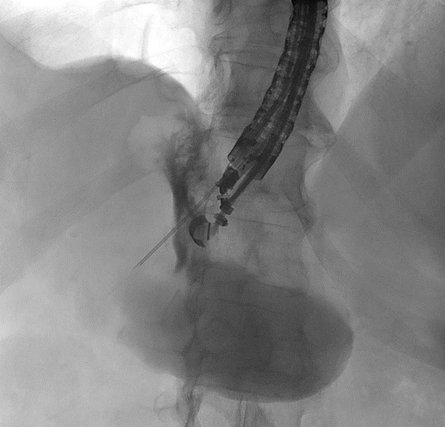

Eine Patientin stellte sich bei uns mit Beschwerden durch Gallensteine im Gallengang vor. Aufgrund der vorangegangenen Magenbypass-Operation war die Papille auf konventionellem endoskopischem Weg nicht erreichbar. Nach ausführlicher Aufklärung entschieden wir uns gemeinsam mit der Patientin für ein modernes, minimal-invasives Verfahren: die sogenannte EDGE-Prozedur (Endoscopic Ultrasound-Directed Transgastric ERCP).

Hierzu wurde zunächst mithilfe der Endosonographie (Ultraschall von innen) der ausgeschaltete Magenanteil aufgesucht. Dieser wurde gezielt punktiert und die korrekte Lage unter Röntgendurchleuchtung mit Kontrastmittel überprüft (Abbildung 1).